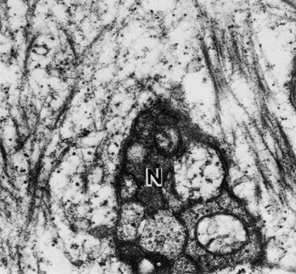

As the midstromal fibers travel toward the central cornea, axons become finer, and beaded features are seen along the filaments prior to their termination. Collaterals from the midstromal fibers branch anteriorly at 90 degrees to create an extensive sub-Bowman's layer plexus. Fibers from the plexus travel anteriorly through Bowman's layer toward the epithelium, where they again turn at 90 degrees and travel parallel to the corneal surface just posterior to the epithelium. Based on confocal microscopy, the majority of fibers in the subbasal plexus of the central cornea appear to be oriented along the superior-inferior axis. There are approximately 5400 to 7200 nerve bundles in the subbasal plexus; because each bundle may contain several axons, the total number of axonal fibers may be as high as 44,000.105 Each fiber immediately forms numerous, elaborate leashes with up to several dozen beaded axon terminals per leash and some additional unbeaded fibers. The beaded appearance was at one time considered an artifact of tissue processing or trauma; however, confocal microscopy has shown these to be genuine features (Fig. 24). The unbeaded straight terminals are not seen entering the epithelium; however, the beaded terminals of the leashes diverge vertically and obliquely among the epithelial cells in a complex manner before terminating at the level of the apical cells (Fig. 25).102 The diameter of the individual nerve fibers in the subbasal plexus are between 0.05 and 2.5 μm with most being in the range of 0.1 to 0.5 μm.

Fig. 25. Nerve axons (N) are visible in the basal cell layer of the epithelium (49,500×). (Courtesy of Drs. Rodrigues, Waring, Hackett, and Donohoo.)